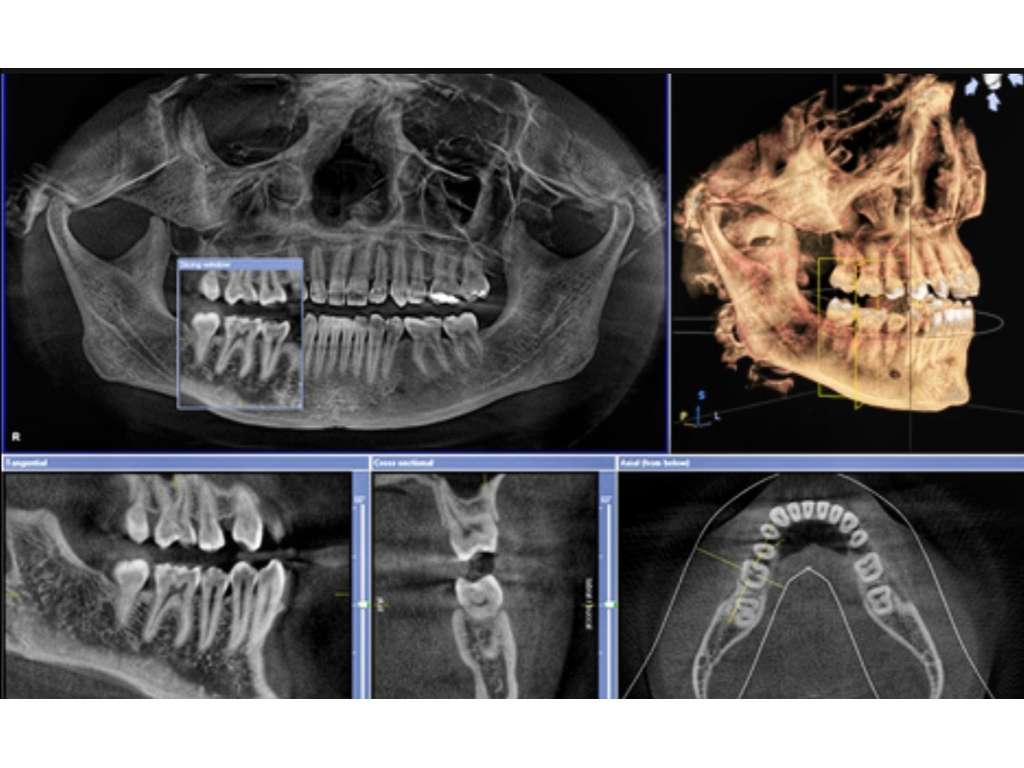

Usluge 3D snimanja

3D snimanje CRANEX 3D aparatom, indikovano i potrebno prilikom ugradnje implantata, kao i za druge dijagnostičke procedure.

Ovim aparatom u potpunjujemo našu uslugu i olakšavamo pacijentima da sve završe na jednom mestu.

Nije potrebno zakazivanje.